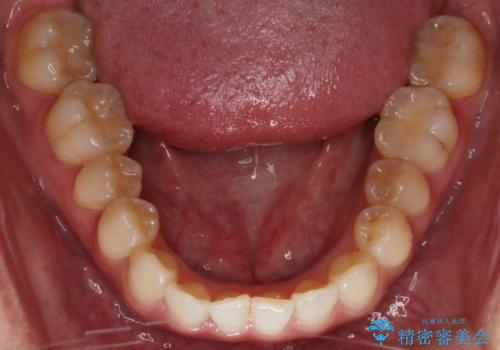

【非抜歯】部分矯正でも治る 前歯の反対咬合

- 前歯にガタつきを主訴にご来院されました。

奥歯の嚙み合わせに問題がほとんどみられなかったため、インビザライン ライトパッケージでの部分矯正を行うこととなりました。

今回のケースでは奥歯の噛み合わせに問題がほぼみられなかったため、前歯の位置のみに焦点を当て部分矯正を行いました。

適応されるケースが限られるものの、適応であった場合の治療期間は全体矯正と比べると格段に短くなり、費用も抑えられます。